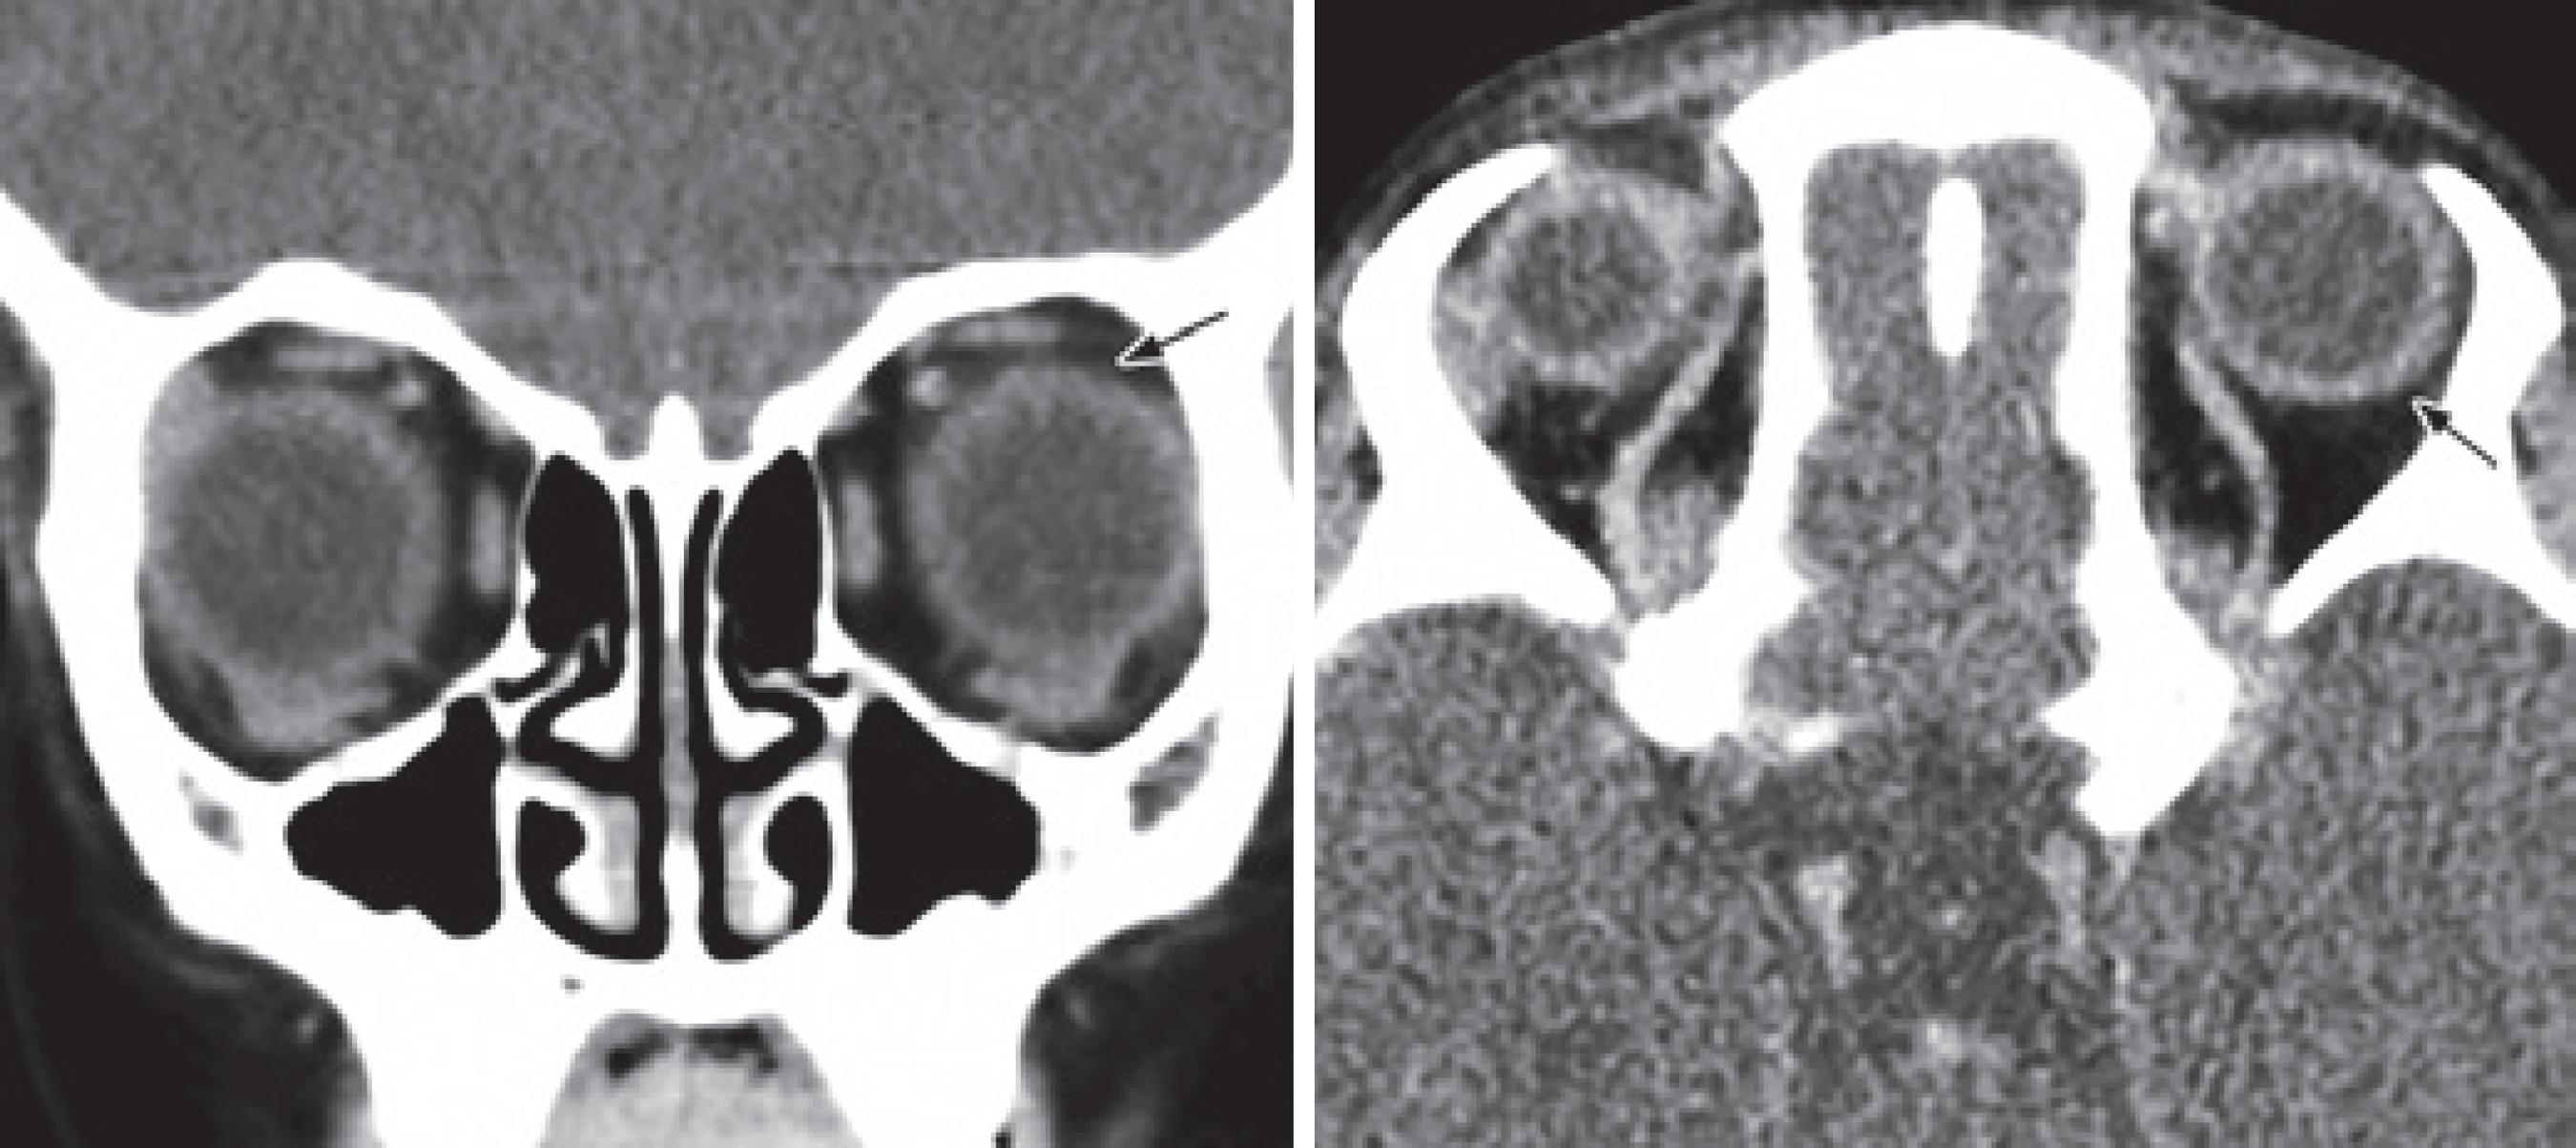

A one-year-old female child was referred to the oculoplastic clinic for severe congenital ptosis surgery of the left eye. On examination, the lid crease was absent, margin reflex distance (MRD1) was 0, and LPS function was poor (less than <5 mm). Eye motility was normal, and Bell's sign was positive. The ocular surface was normal. The patient underwent levator resection surgery, which was described as maximal. Post-operatively, she had good lid height and contour, but the parents noticed she had no tears from her left eye when she cried. Lubricants were prescribed, and she was lost and not followed up. Two years later, she presented with a margin reflex distance of 2.5 mm OU and severe superficial punctate keratitis in the left eye. Computed tomography indicated the absence of the left lacrimal gland (Figure 1).